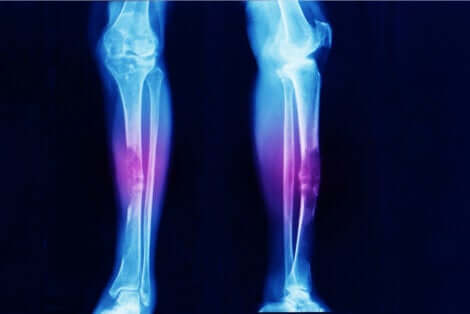

Osteosarcomen en synoviale sarcomen zijn kwaadaardige tumoren van de botten die zich meestal manifesteren nabij de knieën.

- Osteosarcoom, zoals de naam al aangeeft, is botkanker.